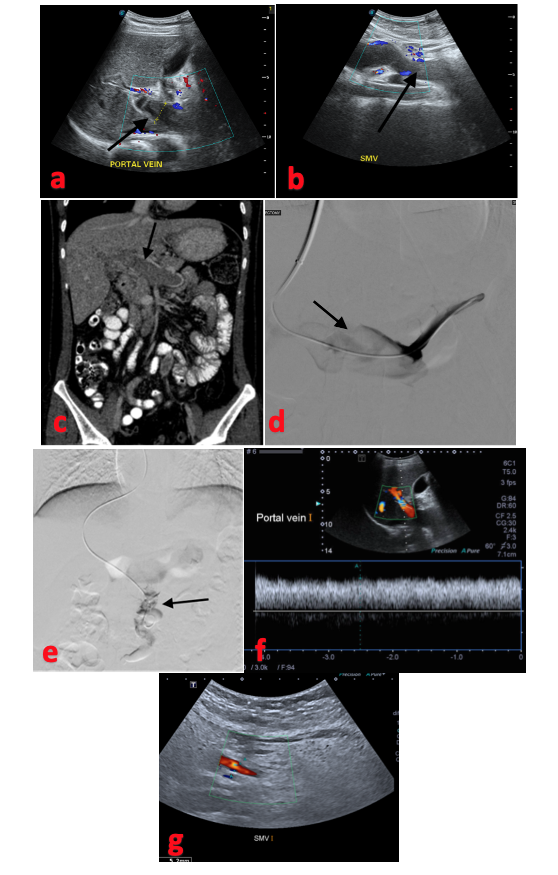

Thrombolysis was done by creating a TIPS/ direct intrahepatic portocaval shunt tract using Artis zee (Siemens Healthineers) and ultrasonography guidance (SonoScape), as described by Keshava et al.16 The right internal jugular vein was accessed under ultrasonography guidance. A modified Rosch-Uchida transjugular liver access set (RUPS-100; Cook Medical) was used to create a tract from the right hepatic vein to the right branch of the PV under ultrasonography and fluoroscopic guidance. In 1 patient (Patient 2) with irreparable hepatic veins, a direct tract from the inferior vena cava to the right branch of the PV was created. A 0.035" hydrophilic Glidewire (Terumo) was then passed into the SMV through the thrombus, and the thrombus was laced. The parenchymal tract was then balloon-plastied using a 10 mm x 4 cm Advance ATB PTA Dilatation Catheter balloon (Cook Medical). Self-expanding stents were deployed in patients 1, 2, and 3. Uncovered Zilver stents (Cook Medical) were deployed in Patient 1 and Patient 3. A Viatorr e-PTFE covered stent (Gore) was deployed in Patient 2. Using a 4F pigtail catheter (Cordis), thrombus was fragmented followed by suction thrombectomy using a 6F Envoy guiding catheter (Cordis). Pharmacological thrombolysis was performed in 4 patients (Patients 3,4,5, and 6) using continuous urokinase infusion of 50,000 units per hour for 48 hours and 100,000 units per hour from 48 to 2 hours via a 5F Mistique infusion catheter (Merit Medical) or 5F pigtail catheter (Cordis). In 5 patients, therapeutic heparinization was done with subcutaneous LMWH, 60 mg every 12 hours.

In Patient 6, there was right hepatic vein ostial narrowing. The hepatic vein was recanalized using a transjugular liver biopsy cannula, a 0.035" hydrophilic Glidewire, and a 4F multipurpose catheter (Cordis) using ultrasonography guidance.17

A portogram was done after infusion on the following day, followed by once every 24 hours. Repeat balloon plasty and further continuation of urokinase infusion was done based on recanalization status. Serial Doppler ultrasound surveillance was done during the initial week every 24 hours to look for thrombosis. After discharge, follow-up Doppler was done at 1 month, 3 months, and thereafter every 6 months. Four patients showed clinical improvement and were discharged from the hospital after 1 week. Two patients (Patients 5 and 6) showed clinical worsening despite PV recanalization, developed signs of bowel ischemia on follow-up CT after day 5, and showed signs of peritonitis. One patient underwent explorative laparotomy and 60 cm of gangrenous small bowel was resected. He was subsequently discharged in stable condition. The other patient was not operated on considering the high risk of mortality due to underlying chronic liver disease and was given best supportive care. However, he expired after 3 days.

Gipson et al described 3 types of image-guided techniques for creation of a TIPS: (1) fluoroscopic guidance with portography (contrast medium or carbon dioxide); (2) marker wire guidance; and (3) ultrasound (US) guidance.30,31 Since the PV is thrombosed, after puncture of the PV, there will not be backflow through the needle to confirm it. We used transabdominal ultrasonography to gain the PV access. Even in a nonthrombosed vein, we use transabdominal US guidance to gain the PV access, as the needle can be visualized in real time and the course of the needle can be tracked.32